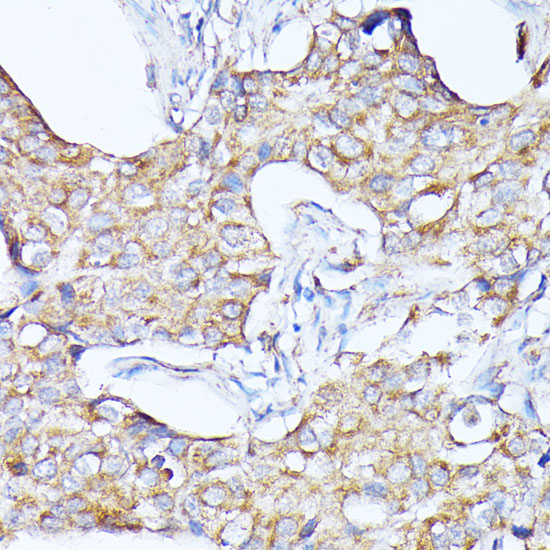

Immunohistochemistry of paraffin-embedded human breast cancer using CTSF at dilution of 1:100 (40x lens).